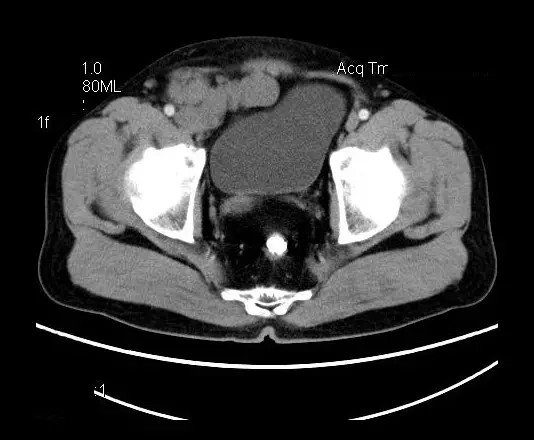

【影像表现】

盆腔右前侧及邻近腹股沟区可见多发大小不等的聚集生长的结节影,病灶呈软组织密度,边缘尚规整,分界尚清,增强扫描可见不均匀强化。膀胱局部受压,盆腔未见明显肿大淋巴结影。